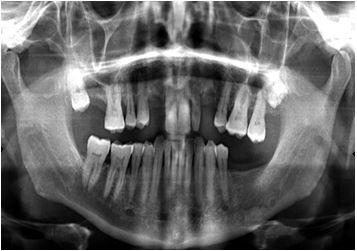

Background and Aim: The styloid process (SP) is a cylindrical bony projection that originates from the inferior part of the petrous temporal bone, directly in front of the stylomastoid foramen. Numerous ligaments, muscles, and nerves are intimately associated with the (SP). When the measurement is more than 30 mm, it is deemed elongated. ES which is typified by a variety of neck and head pains, as well as tinnitus, earache, trigeminal neuralgia, and headache, is related to the elongation of the SP (ESP).The reason of the survey was to look into the ESP prevalence, shape, and calcification pattern in the Yemeni community in Sana'a City, as well as how these factors relate to subgroups and gender.

Methods: This study explored OPG of 1176 Yemeni subjects over the age of 14 years. Some radiograph together with a suspected SP was disregarded from the study. The obvious SP length was calculated by a single qualified maxillofacial and dental radiologist. The distributions of the SP according to sex, age, different types, styloid process length classifications, and differences in the mean length of the ESP in Yemenis were calculated.

Results: The study screened Yemenis for Eagle syndrome, with 35% males and 65% women, with 49.3% having the condition. Styloid process elongation was categorized into elongated type I (20.4%), segmented type III (15.4%), pseudoarticulated type II (2.9%), and type IV elongation due to distant ossification (4.3%). The mean length of the ESP was 29.97±8.17 mm, with no significant differences detected in different age groups.

Conclusion: With or without symptoms, panoramic radiographs are a cost-effective, readily available, and practical diagnostic technique for the early identification of an extended styloid process. Larger sample sizes, however, would be useful in determining how common this extended styloid process is among Yemenis in different areas.